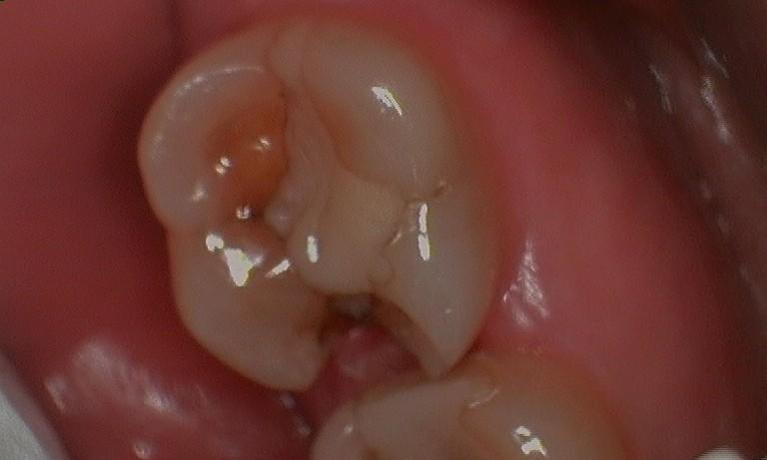

Here is a patient’s molar with a large silver filling with multiple cracks throughout. The patient was beginning to have sensitivity when chewing food. We suspected there was a crack in the tooth. Because the filling was showing such wear and because the tooth was becoming sensitive, we recommended a crown (cap). When we removed the old silver filling, we noticed the crack (noted by the red arrows). Given enough time this crack would have propagated (similar to a crack in a windshield) and the tooth would have broken in half down to the nerve. After placing the tooth-colored ...